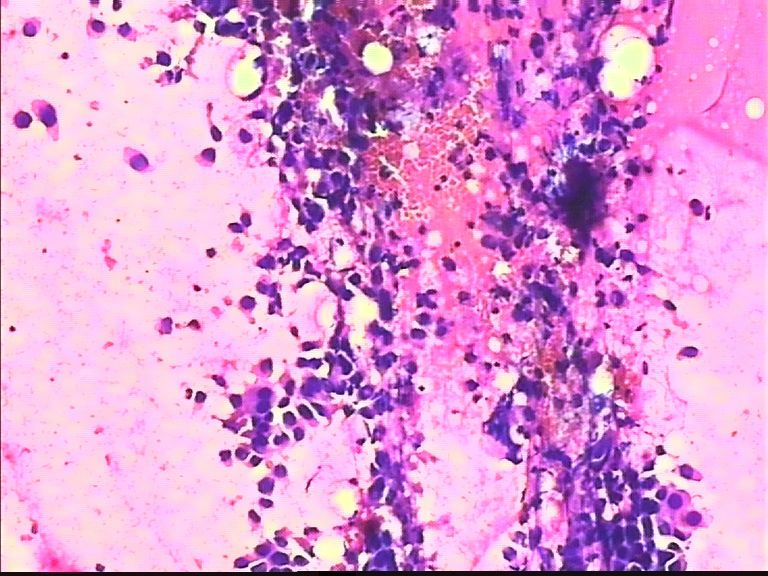

38岁 乳腺肿瘤 女

• 38岁 乳腺肿瘤 女图1

图1

恶性肿瘤细胞

导管癌

乳腺导管癌

非常明显的恶性肿瘤细胞,倾向浸润性导管癌。细胞异型性大,非常弥散,未见肌上皮细胞。

润性导管癌,细胞大小不一、异形明显、粘附性差,尤其是在同一堆细胞内。